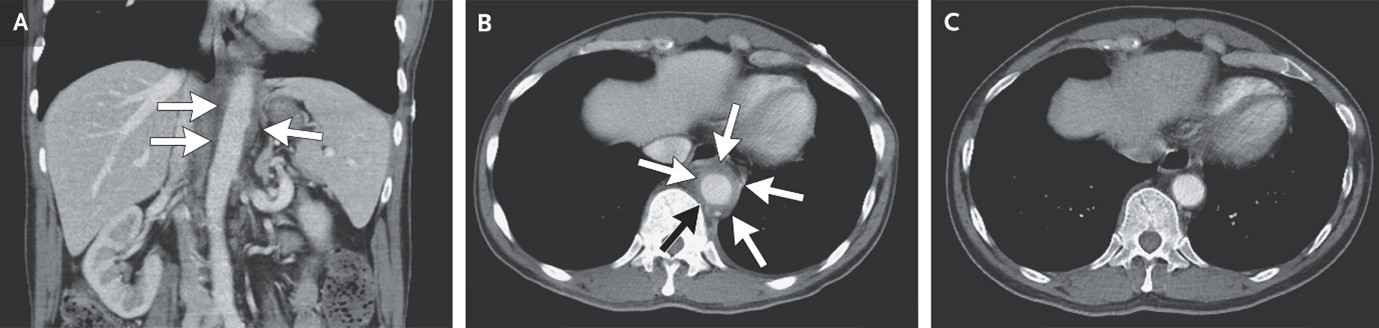

(9). Aortitis Due to Large-Vessel Vasculitis

Hsien-Tzung Liao, Published January 31, 2026, N Engl J Med 2026;394:588, DOI: 10.1056/NEJMicm2513456, VOL. 394 NO. 6

Abstract

A 63-year-old man presented with a 3-month history of chest tightness, palpitations, and abdominal pain. Laboratory studies showed an elevated erythrocyte sedimentation rate and an elevated C-reactive protein level.